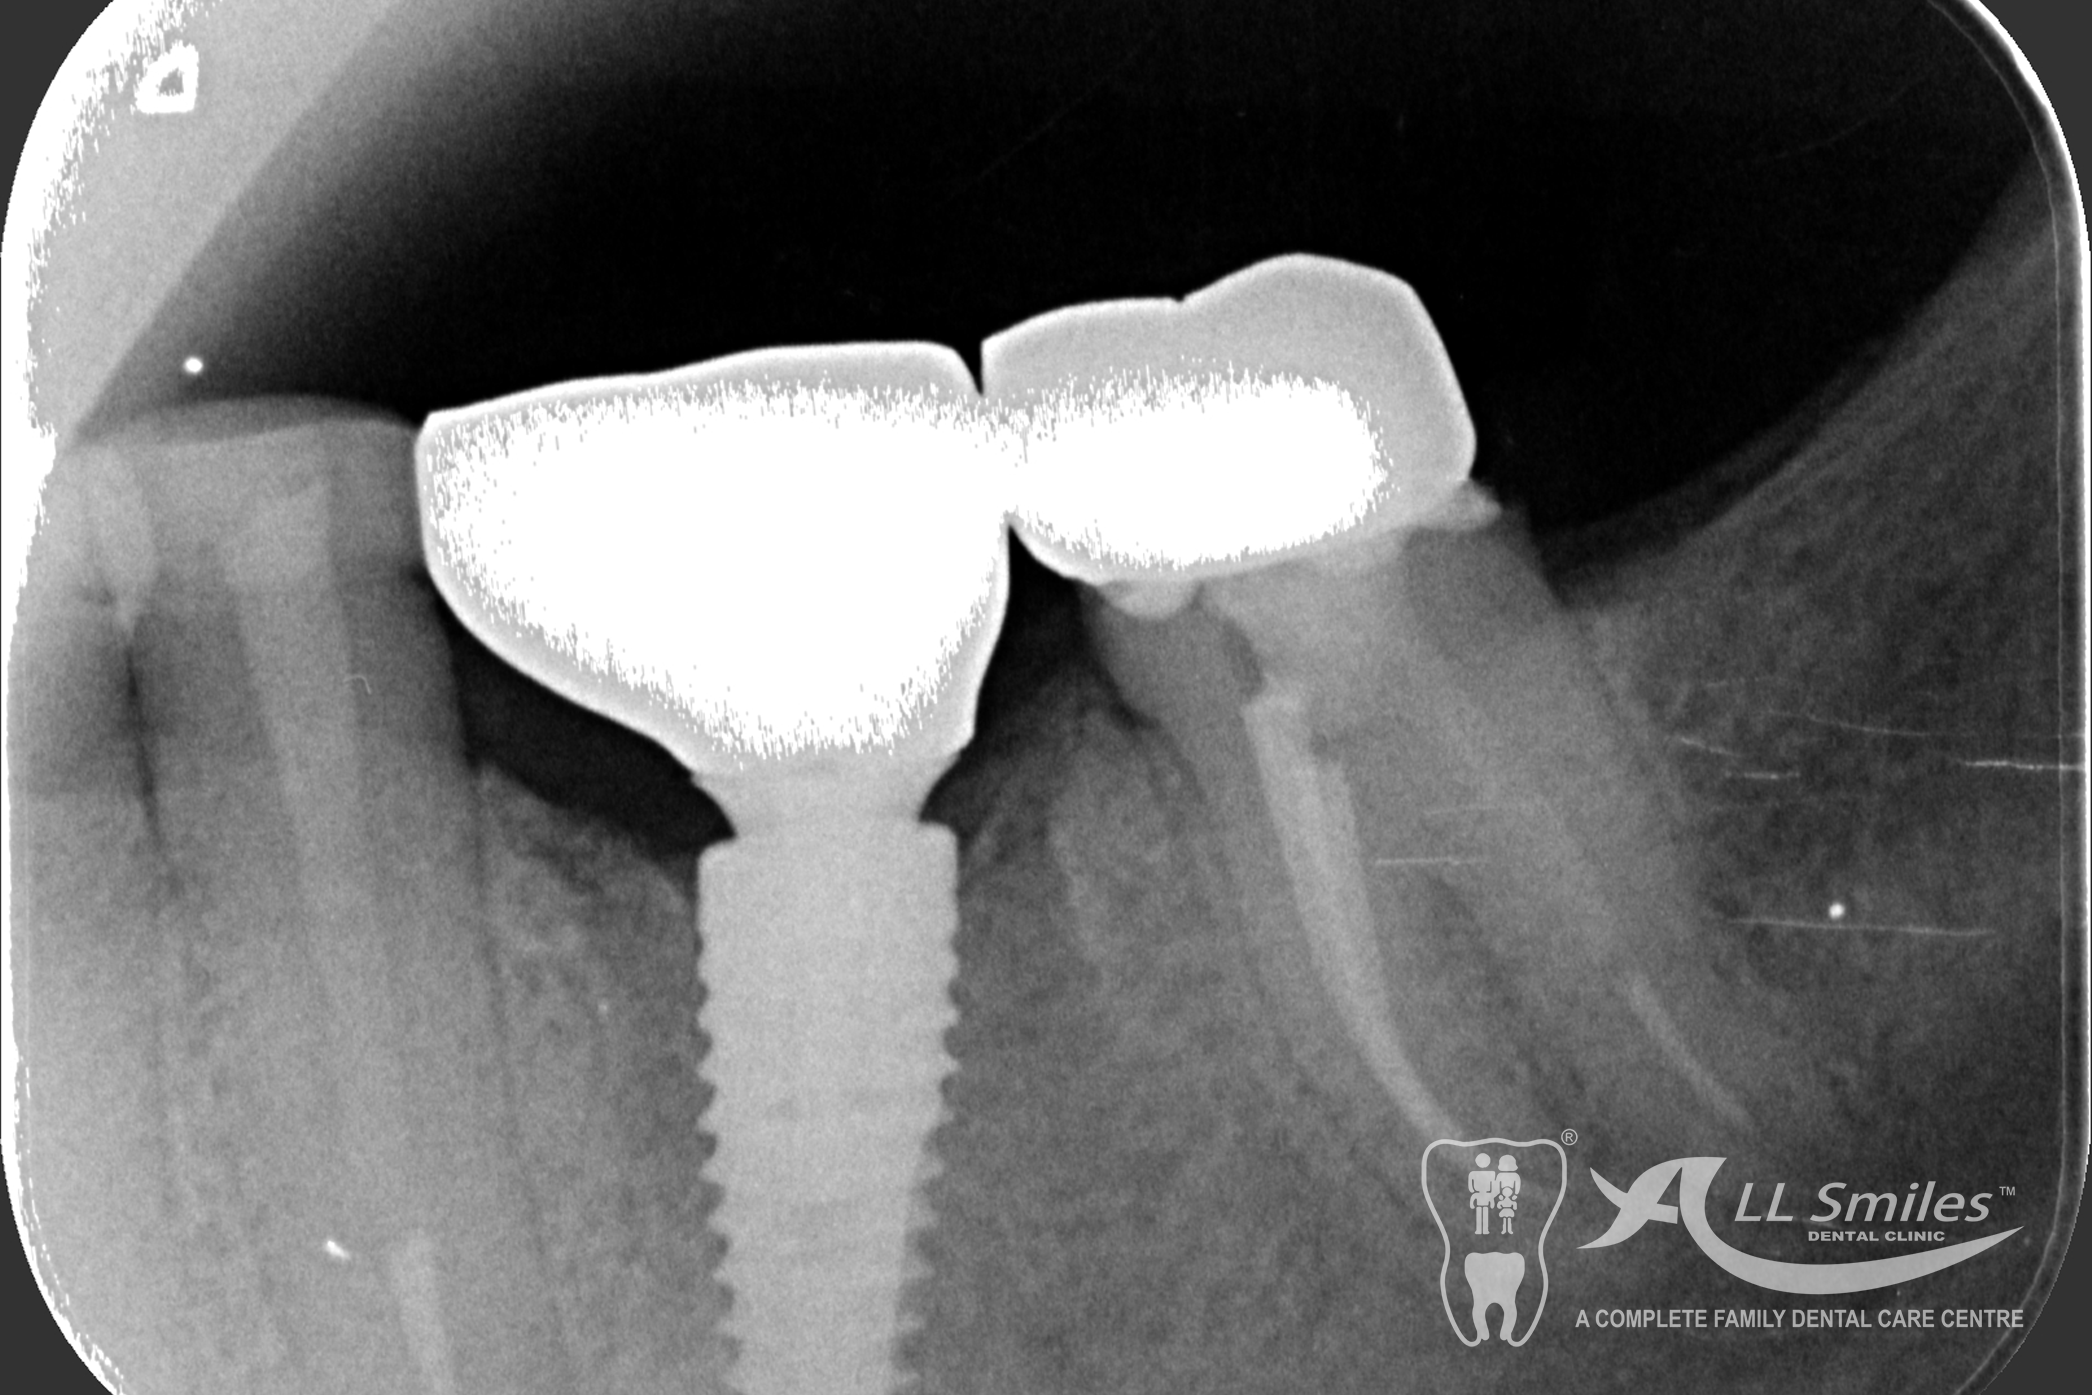

Anyone can lose a tooth. It often happens in seconds: playing sport and a tooth is gone, just like that. A shock , but no great drama any more. Implants resolve the small problem naturally and invisibly. We insert the small high-tech root at the position where the natural tooth was in the jaw.

This usually does not take any longer than any routine treatment. A temporary restoration closes the gap until the implant is healed. Then the final tooth crown is fixed in place – permanently . With the new root it is fixed firmly in the jaw and feels identical to your natural teeth.

The dental implant procedure is divided into stages. The first stage involves the placement of the implant into the jawbone, which usually takes 1-2 hours. After this, there is a healing period of 6-8 weeks during which the implant fuses with the surrounding bone tissue. Once the implant has healed, a small connector called an abutment is attached to the implant, followed by the attachment of a dental crown, bridge, or denture.